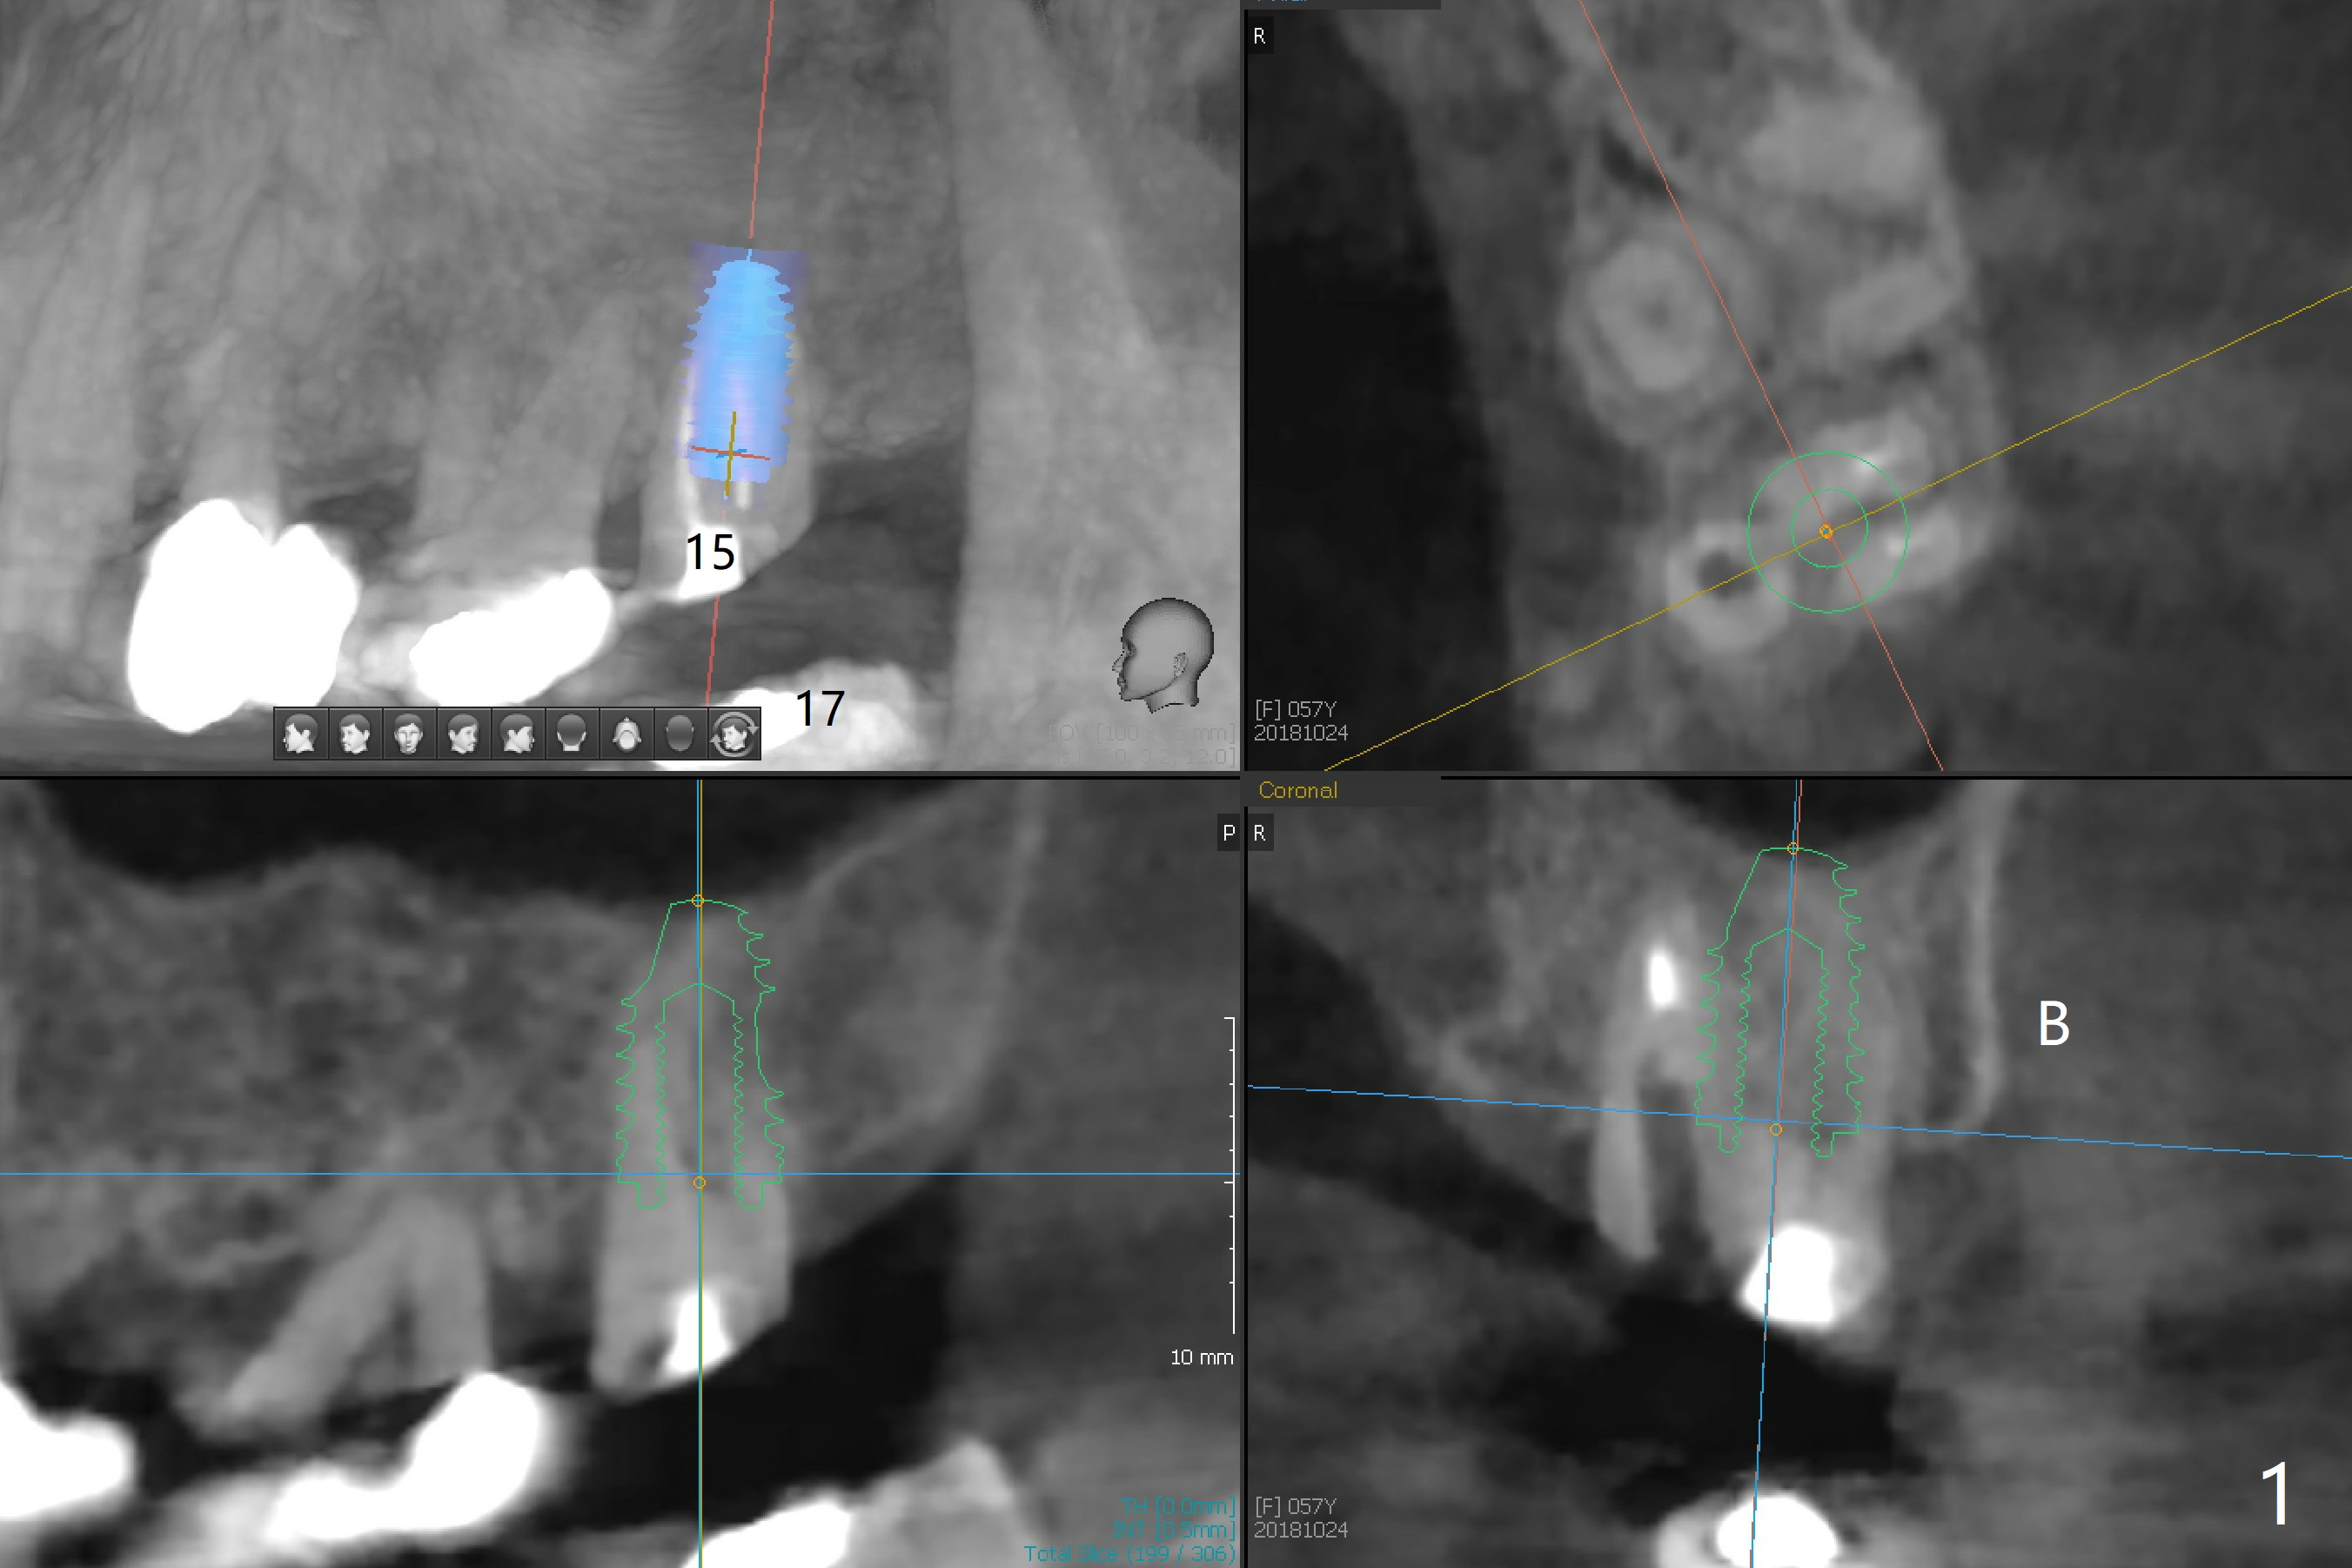

Occlusal Interference from Supraerupted Lower 3rd Molar

A 58-year-old woman wants to have an implant at #15 after placement of those at #2 and 4 (Fig.1). Restoration height is limited by the supraerupted tooth #17. Occlusal reduction is expected if an immediate provisional is fabricated. A 5x8.5 mm implant will be placed in the septum or the buccal socket. A 5x14 mm tissue level implant will be placed to reduce screw loosening associated with bruxism and torus palatinus (Fig.2,3).